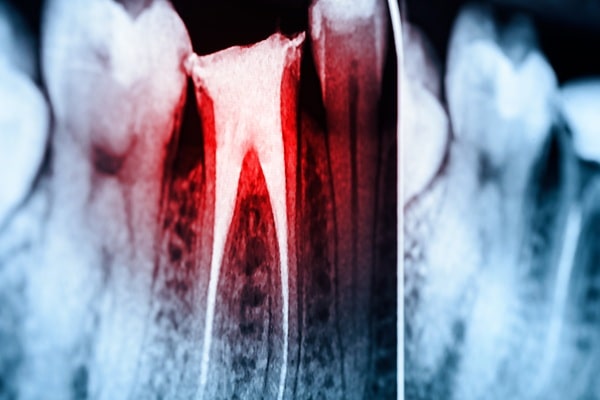

Diagnosis & X-Rays

We assess the tooth and confirm if a root canal is necessary.